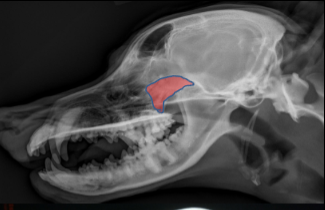

Coronoid Process of Mandible

ID Radiographic View